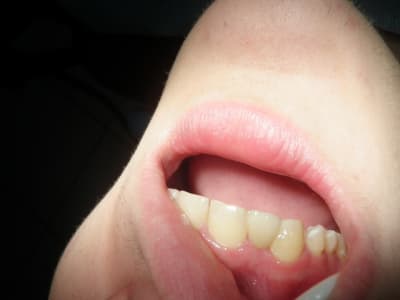

bonjour, le cas :

Dsc00091 vo4p11 - Eugenol

rebonjour, le provisoire : excuse pour la qualité des photos

(sony cybertshot première génération 2.1mp....)

amha le bridge collé c'est pas l'indication dans un cas comme ça.